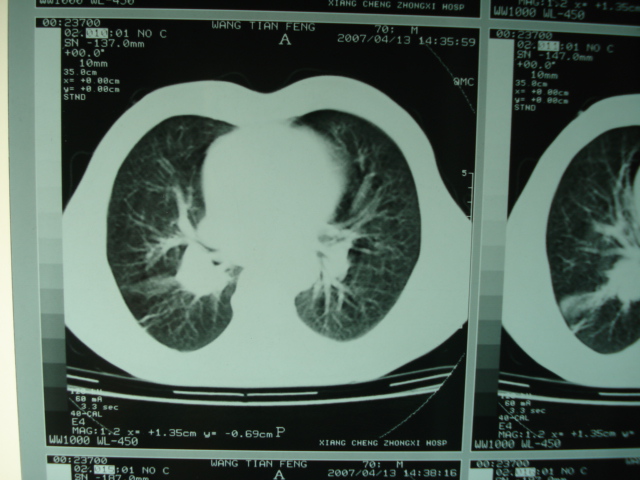

以下是引用狙击手在2007-4-18 20:17:00的发言:[br]原:2007/1/22号ct片:右肺上叶可见片状、云雾状高密度影,右肺上叶后段可见三角形高密度影,尖端指向肺门,右肺上叶后段支气管壁不规则增厚,管腔不规则增厚,纵隔未见肿大淋巴结.[br] 今ct:右肺上叶片状影增大,右肺上叶后段不张及右肺上叶后段支气管壁不规则增厚未见变化,右肺下叶背段支气管壁不规则增厚.[br] 如果考虑肺结核,但从临床证据看竟然没有一项支持肺结核,不知患者是否已经过正规抗结核治疗。没有的话,3个月了前后片看起来变化不大,似乎有不太符合肿瘤征象,不知患者是否抗炎治疗过,下叶支气管增粗还是要高度警惕,同意楼主意见,将常规病理,生化检查再做一遍。[br]

以下是引用狙击手在2007-4-18 20:17:00的发言:[br]原:2007/1/22号ct片:右肺上叶可见片状、云雾状高密度影,右肺上叶后段可见三角形高密度影,尖端指向肺门,右肺上叶后段支气管壁不规则增厚,管腔不规则增厚,纵隔未见肿大淋巴结.[br] 今ct:右肺上叶片状影增大,右肺上叶后段不张及右肺上叶后段支气管壁不规则增厚未见变化,右肺下叶背段支气管壁不规则增厚.[br] 如果考虑肺结核,但从临床证据看竟然没有一项支持肺结核,不知患者是否已经过正规抗结核治疗。没有的话,3个月了前后片看起来变化不大,似乎有不太符合肿瘤征象,不知患者是否抗炎治疗过,下叶支气管增粗还是要高度警惕,同意楼主意见,将常规病理,生化检查在做一遍。[br]